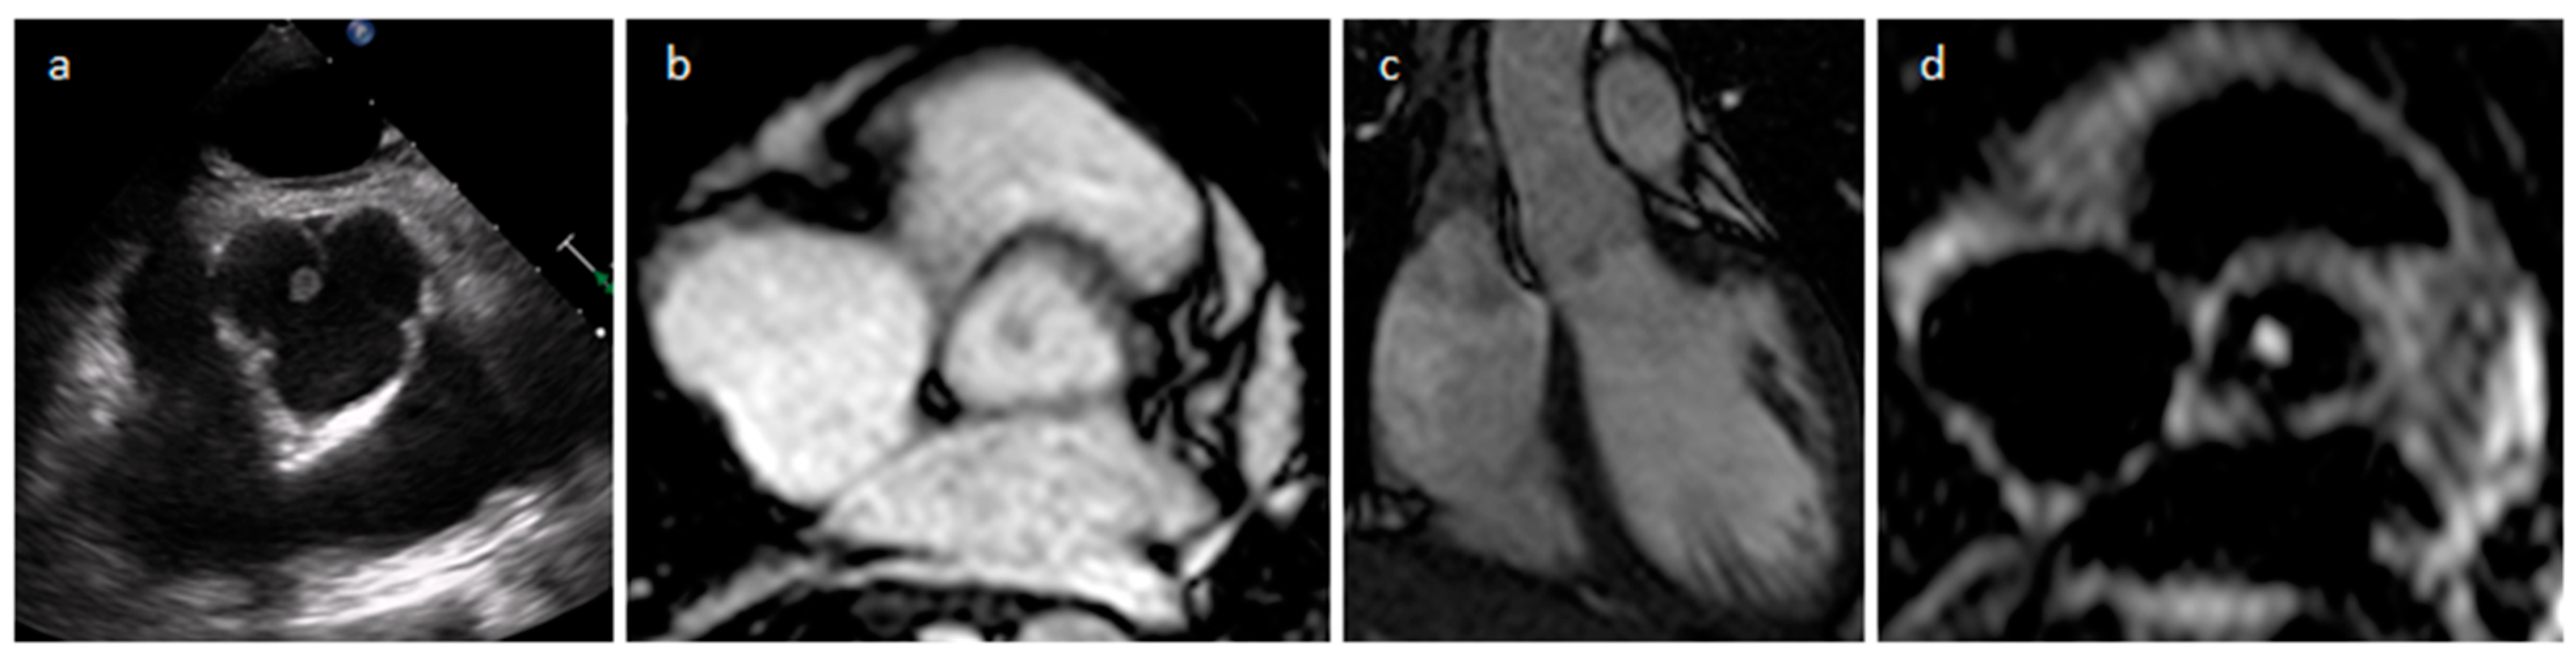

4.2. Papillary Fibroelastoma (PFE)

| Papillary fibroelastoma | Adulthood | Valves | Usually, asymptomatic. Rarely embolic events | Atrial side of the mitral valve or the aortic surface of the aortic valve leaflet | Stippling and vibration or shimmer of the peripheral edge. | Hypodense, smooth, peduncolated, attached to the valve leaflet by a short pedicle | Iso T1w, Hyper T2w, hypo cine with surrounding turbolent flow, poor LGE |